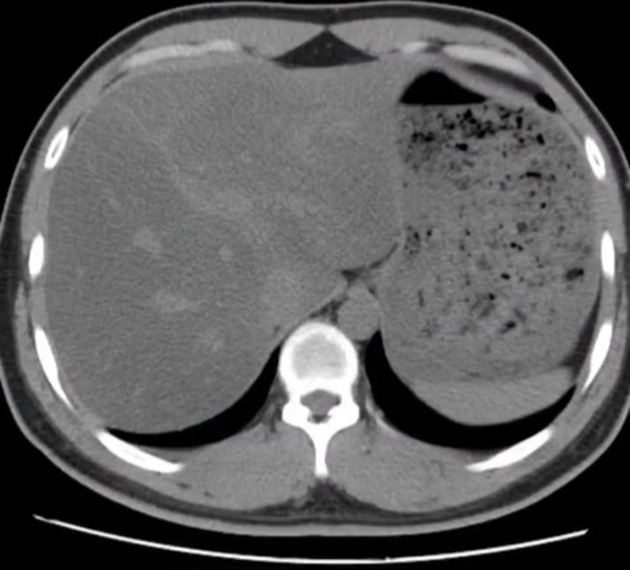

Sau vài tháng, cô giảm được 10kg, vòng eo nhỏ lại rõ rệt. Tuy nhiên, kết quả tái khám sau 6 tháng ăn như vậy lại khiến cô ngỡ ngàng. Dù chỉ nặng 47kg nhưng tình trạng gan nhiễm mỡ nhẹ không những không giảm đi mà tăng lên 2 cấp độ, đạt tới mức nặng kèm suy giảm chức năng thải độc gan và có sỏi thận nhỏ. Cô cũng bị suy giảm miễn dịch, rối loạn nội tiết (rụng tóc, chậm kinh) do ché độ ăn này.

Trường hợp của cô Phạm thuộc nhóm đầu tiên. Sai lầm lớn nhất là cắt bỏ hoàn toàn protein và chất béo. Cơ thể con người cần sự cân bằng của nhiều nhóm dinh dưỡng. Khi thiếu protein nghiêm trọng, gan không đủ nguyên liệu để tạo ra các chất vận chuyển mỡ ra khỏi gan.

Hệ quả là mỡ bị giữ lại và tích tụ ngày càng nhiều. Đây là gan nhiễm mỡ do thiếu dinh dưỡng. Việc giảm cân quá nhanh còn khiến cơ thể rơi vào trạng thái đói giả. Nguồn năng lượng dự trữ bị huy động dồn về gan, khiến gan quá tải và nhiễm mỡ nặng hơn.